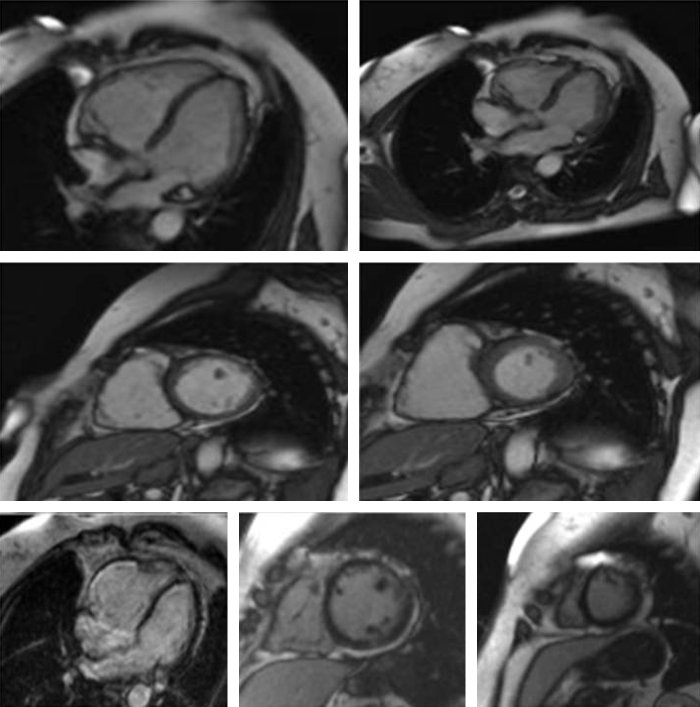

In ambito cardiologico la RM viene richiesta per molteplici ragioni tra le quali il riconoscimento e la quantificazione dell’ischemia miocardica, delle cardiomiopatie sia congenite che acquisite, delle miocarditi e delle patologie del pericardio e rappresenta l’indagine di primo livello nella quantificazione della fibrosi cardiaca e delle cicatrici miocardiche.

La sua elevata definizione consente inoltre un appropriato studio delle sezioni destre del cuore spesso di difficile valutazione con altre metodiche, ecocardiografia compresa. Qualora la tecnica venga applicata al distretto vascolare, generalmente per la definizione di anomalie di decorso o diametro di arterie, si parla di ANGIORM specificandone il distretto (ad es cerebrale, toracico, addominale…).